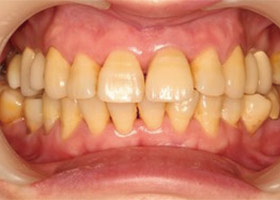

假牙完成後,門牙特寫、切端特寫照,暴牙已不復見。